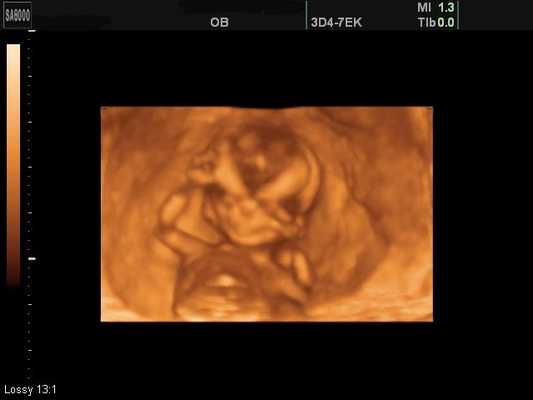

Поверхностный режим 3D/4D УЗИ позволил визуализировать поверхности тела плода (лоб, лицо, переднюю поверхность груди, область половых органов, затылок и заднюю поверхность спины, дистальные отделы конечностей, суставы конечностей) при сроках гестации 11-22 недель в большинстве случаев (93%) (рис. 1-4). Затруднения в визуализации отдельных поверхностей были отмечены в 24% из-за особенностей положения плода, расположения конечностей и других частей тела, локализации пуповины, количества околоплодных вод. Двигательная активность плода и многоводие значительно облегчали задачу визуализации поверхностей. Следует также учитывать, что полное отсутствие околоплодных вод во всех случаях не позволило получить информацию о поверхностях у плода в этом режиме. Сложности в получении поверхностных изображений отмечены в 38% случаев при обследованиях плодов после 35 недель гестации.

Рис. 1. Беременность 12 недель (поверхностный режим). Лицо здорового плода.